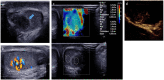

Pre- and post-pubertal testicular tumors are two distinct entities in terms of epidemiology, diagnosis and treatment. Most pre-pubertal tumors are benign; the most frequent are teratomas, and the most common malignant tumors are yolk-sac tumors. Post-pubertal tumors are similar to those found in adults and are more likely to be malignant. Imaging plays a pivotal role in the diagnosis, staging and follow-up. The appearance on ultrasonography (US) is especially helpful to differentiate benign lesions that could be candidates for testis-sparing surgery from malignant ones that require radical orchidectomy. Some specific imaging patterns are described for benign lesions: epidermoid cysts, mature cystic teratomas and Leydig-cell tumors. Benign tumors tend to be well-circumscribed, with decreased Doppler flow on US, but malignancy should be suspected when US shows an inhomogeneous, not-well-described lesion with internal blood flow. Imaging features should always be interpreted in combination with clinical and biological data including serum levels of tumor markers and even intra-operative frozen sections in case of conservative surgery to raise any concerns of malignity. This review provides an overview of imaging features of the most frequent testicular and para-testicular tumor types in children and the value of imaging in disease staging and monitoring children with testicular tumors or risk factors for testicular tumors.